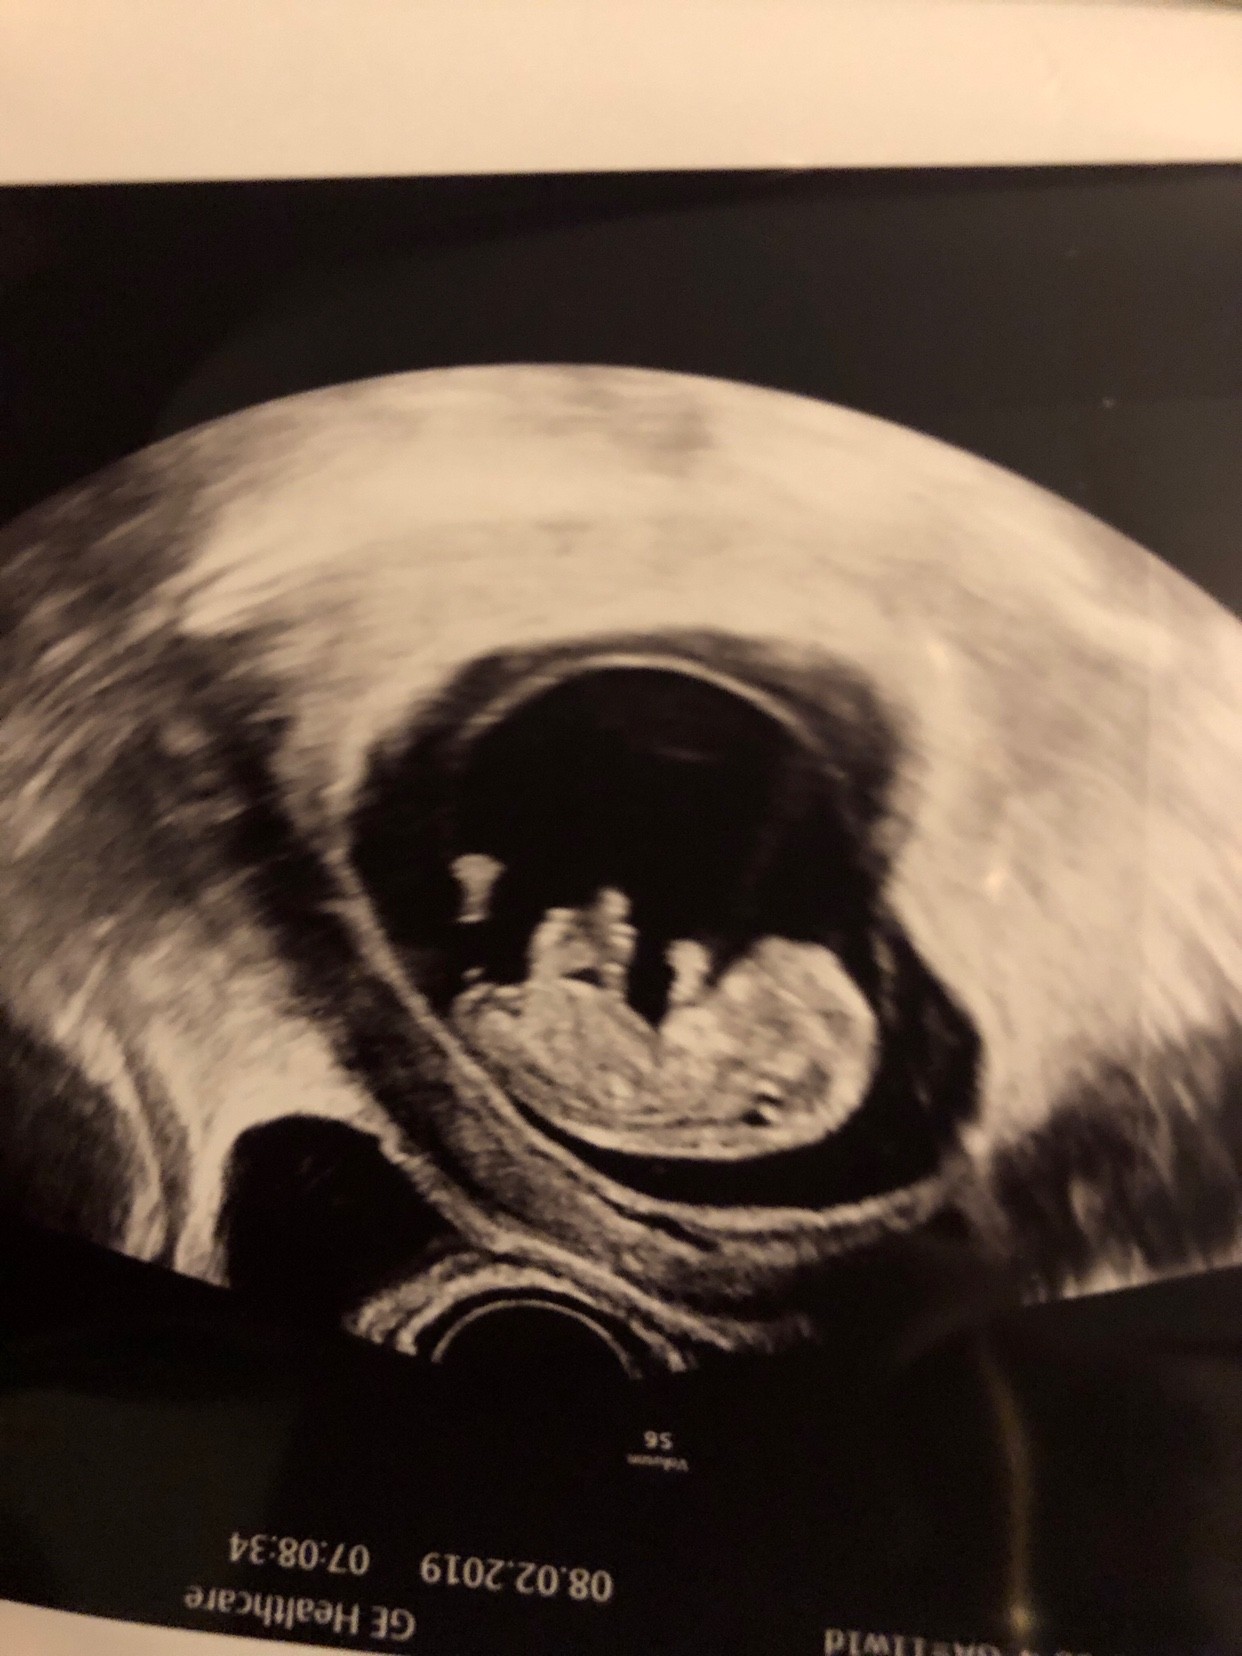

Nasz malutek [emoji177]